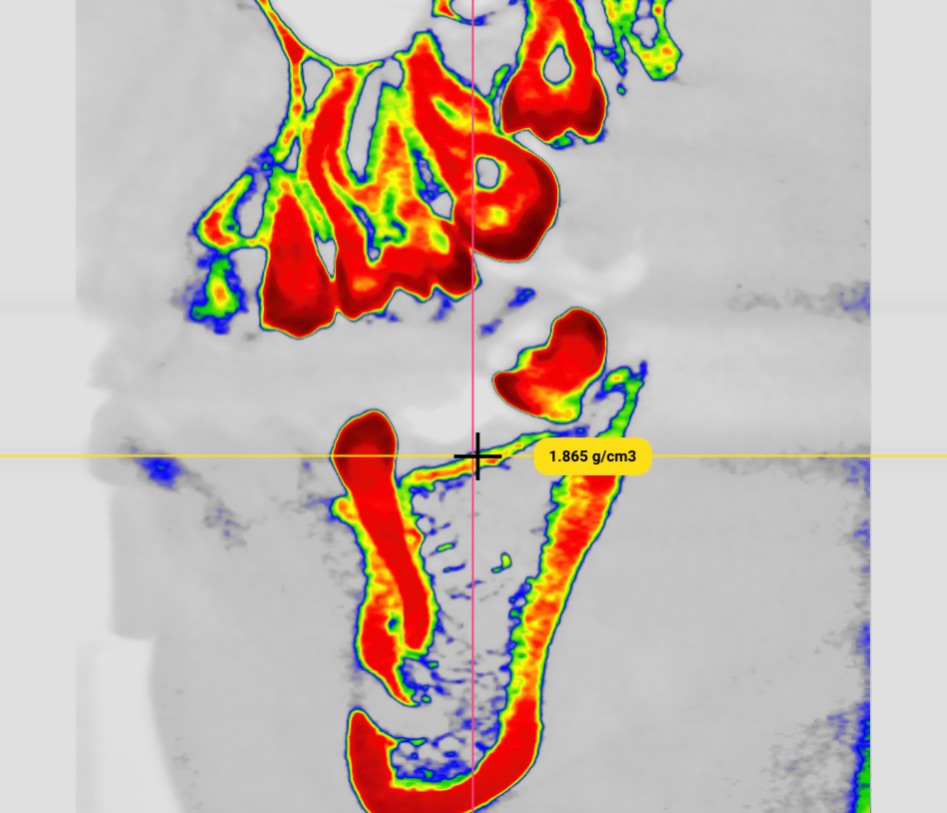

Cone Beam Computed Tomography (CBCT) revealed:

- Severely atrophic maxilla consistent with Cawood and Howell Class VI

- Residual bone height: <5 mm in most regions

- Residual bone width: <4 mm

- Inadequate bone volume for placement of endosseous implants without augmentation

- Finite Element Analysis (FEA) for stress distribution assessment